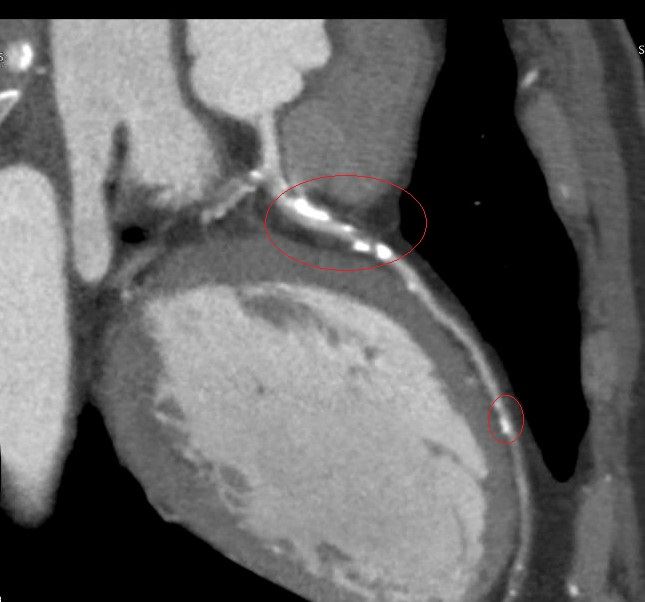

李學林表示,49歲林姓男子日前接受肺癌篩檢(LDCT),意外發現心血管鈣化,但無法確認是血管內或血管外鈣化,考慮到患者平時已出現胸悶症狀,進一步做心臟冠狀動脈電腦斷層,確認為3條主要冠狀動脈血管內鈣化狹窄達85%以上,若未及時處理,隨時可能引發急性心肌梗塞。

李學林指出,醫療團隊透過心導管手術搭配血管內震波碎石術(IVL),利用震波氣球貼近血管壁發出超聲壓力波,擊碎血管壁的堅硬鈣化斑塊,使原本僵硬的血管恢復擴張性,為支架放置創造理想的環境,再植入3支支架,使其完整展開、貼合血管,降低支架血栓及再狹窄風險。

臨床上約有3成冠狀動脈疾病患者伴隨中重度血管鈣化狹窄,鈣化讓血管變硬、難以擴張,造成治療挑戰。相較於傳統治療,如切割球囊或鑽石旋磨術,血管內震波碎石術對血管壁更溫和,有效降低血管破裂與剝離風險,安全性高,但目前該技術尚未納入健保給付。